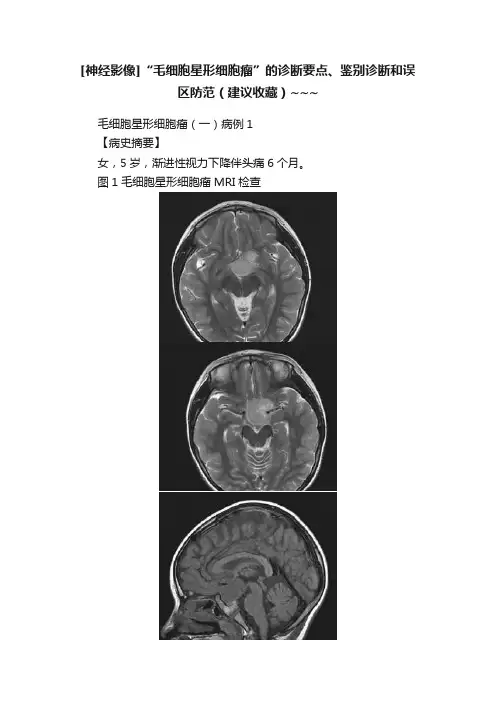

[神经影像]“毛细胞星形细胞瘤”的诊断要点、鉴别诊断和误区防范(建议收藏)~~~毛细胞星形细胞瘤(一)病例1【病史摘要】女,5岁,渐进性视力下降伴头痛6个月。

图1毛细胞星形细胞瘤MRI检查【影像所见】图1A、B、C、D、E、F,平扫见下丘脑区不规则长T1稍长T2肿块,边界清楚,信号稍不均匀,其内可见小囊变区,视交叉及垂体柄显示不清,垂体尚可见。

图1H、I、J、K、L,增强扫描见肿块呈显著不均匀强化,其内可见囊变区;松果体区未见异常强化病灶,垂体均匀强化。

【诊断和分析】本病例诊断为下丘脑毛细胞星形细胞瘤。

影像学诊断要点:①儿童和青少年多见;②下丘脑不规则分叶状肿块,边界清楚,肿瘤内囊变较多见,出血少见;③MRI呈不均匀长T1长T2信号,增强扫描实性部分明显增强,囊变区无强化。